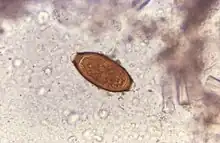

The disease is usually spread when people eat food or drink water that contains the eggs of these worms.[1] This may occur when contaminated vegetables are not fully cleaned or cooked.[1] Often these eggs are in the soil in areas where people defecate outside and where untreated human feces is used as fertilizer.[2] These eggs originate from the feces of infected people.[1] Young children playing in such soil and putting their hands in their mouths also become infected easily.[1] The worms live in the large bowel and are about four centimetres in length.[2] Whipworm is diagnosed by seeing the eggs when examining the stool with a microscope.[3] Eggs are barrel-shaped.[8] Trichuriasis belongs to the group of soil-transmitted helminthiases.[9]

Adult worms are usually 3–5 centimetres (1.2–2.0 in) long, with females being larger than males as is typical of nematodes. The thin, clear majority of the body (the anterior, whip-like end) is the esophagus, and it is the end that the worm threads into the mucosa of the colon. The widened, pinkish gray region of the body is the posterior, and it is the end that contains the parasite's intestines and reproductive organs. T. trichiura eggs are prolate spheroids, the shape of the balls used in Rugby and Gridiron football. They are about 50–54 μm (0.0020–0.0021 in) long and have polar plugs (also known as refractile prominences) at each end.

A stool ova and parasites exam reveals the presence of typical whipworm eggs. Typically, the Kato-Katz thick-smear technique is used for identification of the Trichuris trichiura eggs in the stool sample. Trichuria eggs often appear larger and more swollen on Kato-Katz preparation compared to when using other techniques.[18]

Trichuriasis can be diagnosed when T. trichiura eggs are detected in stool examination. Eggs will appear barrel-shaped and unembryonated, having bipolar plugs and a smooth shell.[20] Rectal prolapse can be diagnosed easily using defecating proctogram and is one of many methods for imaging the parasitic infection. Sigmoidoscopys show characteristic white bodies of adult worms hanging from inflamed mucosa ("coconut cake rectum").[21]